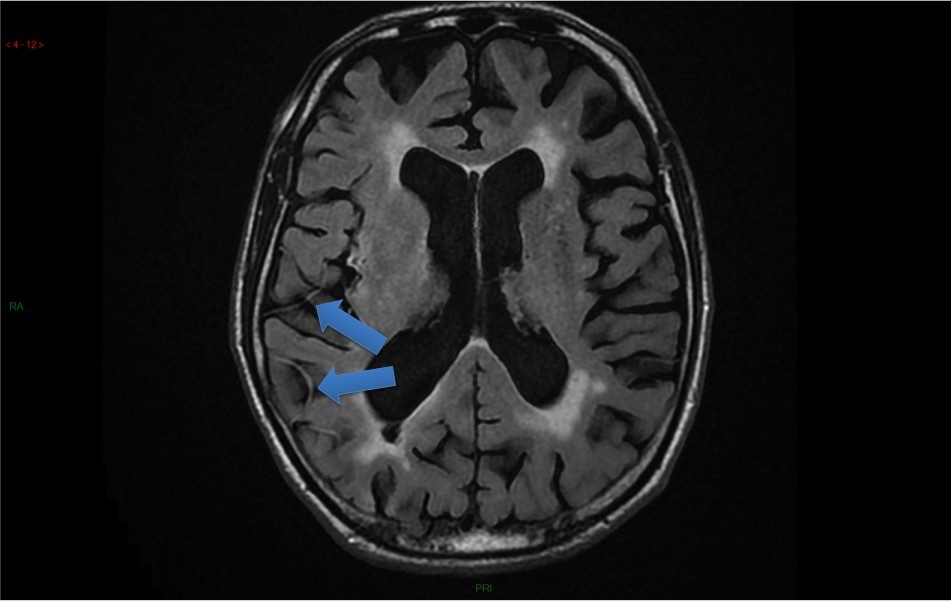

Ci-dessous des coupes axiales Diffusion et Flair de l’IRM cérébrale. La séquence T2* ne présente pas d’anomalie.

Hypersignaux diffusion à la limite de la visibilité en Flair.

L’IRM montre de multiples AVC ischémiques aigus (i. e.  6 heures), corticaux et sous-corticaux, dans des territoires artériels différents.